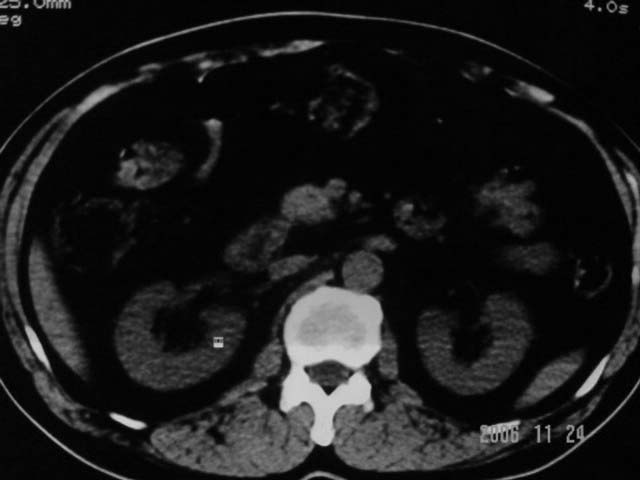

标题: CT5395:男、60岁,皮肤、巩膜黄染伴上腹部疼痛20天 [打印本页]

标题: CT5395:男、60岁,皮肤、巩膜黄染伴上腹部疼痛20天

劳烦各位老师看一下最后一幅箭头指的地方是不是胆总管结石.ct值约63hu.

感觉不是结石可能,与上一层面联系应该是门脉区影像,图像显示不佳,胆总管显示不清[特别是胰头以上段],目前影像只能说肝内外胆管扩张,胰管扩张,胆囊扩大。提示胆总管远端梗阻。可考虑肿瘤或结石所致

胆总管内结节状高密度灶,边缘隐约可见低密度环绕,首先考虑结石伴肝内胆管扩张; 2、胆囊增大,胆囊炎

肝内外胆管及胰管均示有扩张,胆囊增大.提示胆总管远端梗阻,可考虑肿瘤或结石或肿瘤伴结石,建议强化扫描